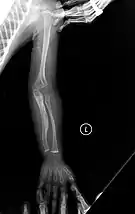

The main symptom of osteogenesis imperfecta is fragile, low mineral density bones; all types of OI have some bone involvement.[5] In moderate and especially severe OI, the long bones may be bowed, sometimes extremely so.[28] The weakness of the bones causes them to fracture easily; a study in Pakistan found an average of 5.8 fractures per year in untreated children.[29] Fractures typically occur much less after puberty, but begin to increase again in women after menopause and in men between the ages of 60 and 80.[1]: 486

Diagnosis is typically based on medical imaging, including plain X-rays, and symptoms. In severe OI, signs on medical imaging include abnormalities in all extremities and in the spine.[97] As X-rays are often insensitive to the comparatively smaller bone density loss associated with type I OI, DEXA scans may be needed.[5]: 1514